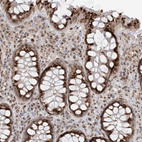

Immunohistochemical staining of human Fallopian tube shows strong granular cytoplasmic positivity in glandular cells.